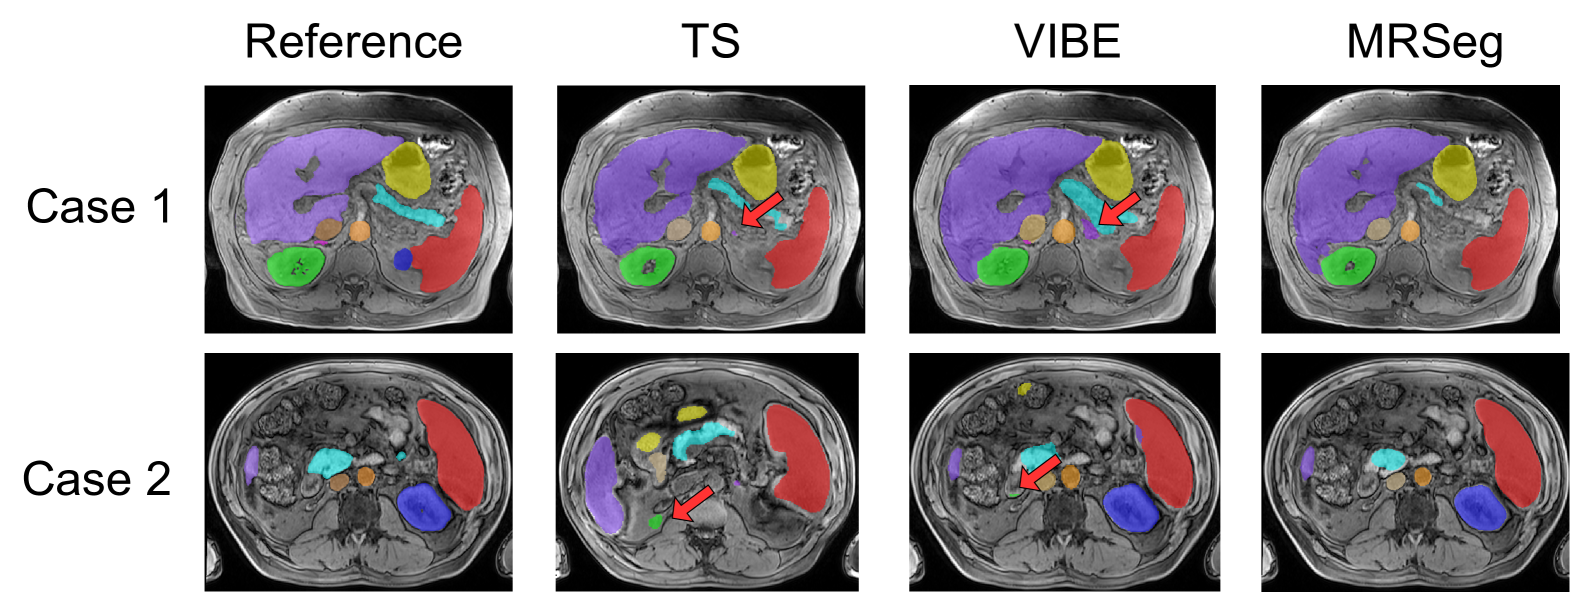

Refer to caption

Figure 10: False positive segmentations for the left adrenal gland (top row, red arrows) and right kidney (bottom row, red arrows) generated by TotalSegmentator MRI (TS) and TotalVibeSegmentator (VIBE). MRSegmentator did not generate any false positives on either case.